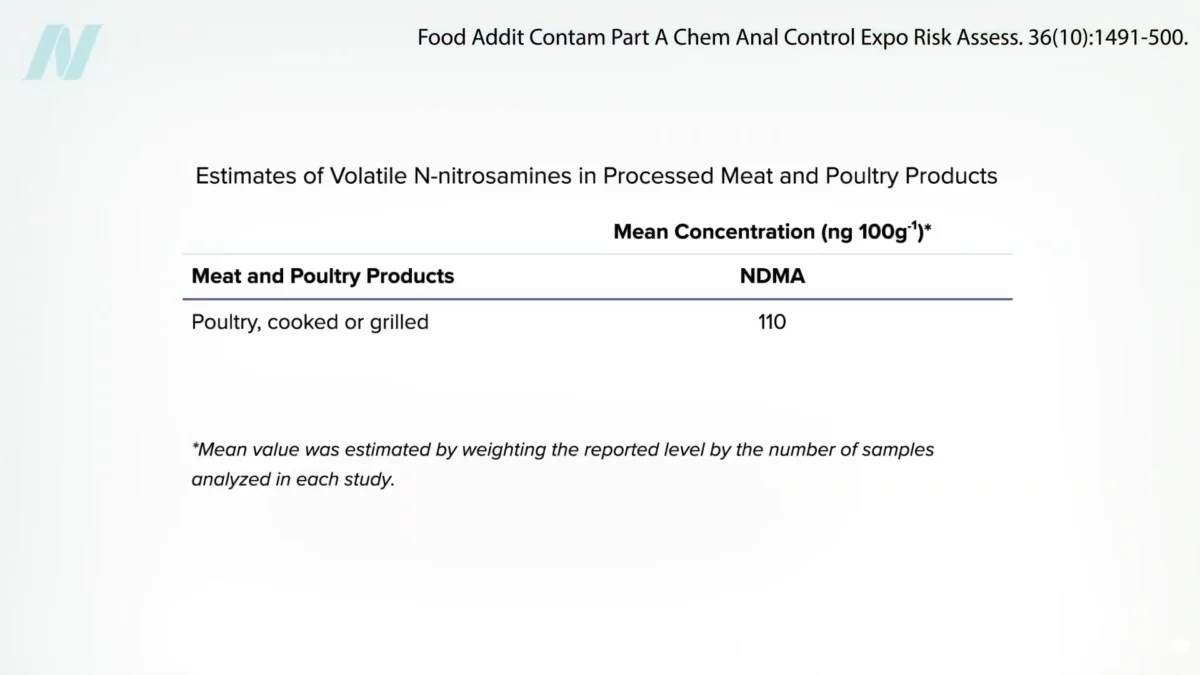

Billion-Dollar Drugs Recalled for Carcinogen Levels Far Exceeding Those Found in Grilled Chicken

In a striking disparity that has raised significant public health questions, billion-dollar pharmaceutical products have been withdrawn from the market due to contamination with N-nitrosodimethylamine (NDMA), a compound classified as…